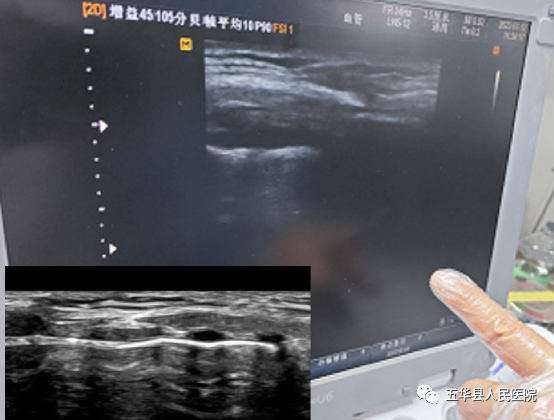

图1.气道超声检查定点穿刺部位 避免损伤重要组织器官